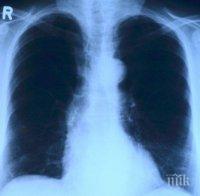

Лекари прогнозират спад в рака на белия дроб с новите алтернативи на цигарите

Лекари прогнозират спад в рака на белия дроб с новите алтернативи на цигарите. Това съобщи испанският ежедневник Cinco Dias, цитиран от „Конкурент”.